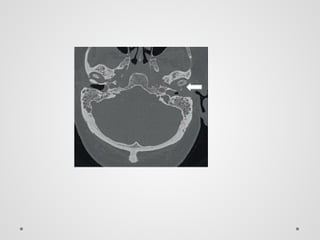

• #43 Computed tomography of the temporal bone in a diabetic patient demonstrating bony erosion of the left anterior ear canal (arrow) and soft tissue filling the external auditory canal (EAC). A large polyp was noted on otoscopic examination of the patient’s EAC.